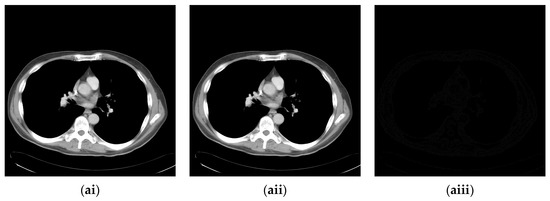

4.2. Experimental Results for Medical Images

Since the interpolation-based RDH schemes are designed for the special purpose of embedding patient information into medical images, the performance of our proposed adaptive RDH scheme on medical images is the main concern. Figure 11 shows the original image and its corresponding confidential image with 2 bpp secret data embedded, and images showing the difference between the original medical images and their confidential images. The difference images (aiii–fiii) in Figure 11 show almost nothing, which indicates that the proposed scheme does not look much different from the original image after hiding and will not draw the eavesdropper’s attention.

Figure 11.

The original images, the confidential images, and the different images; (ai–fi) The cover images; (aii–fii) The confidential images; (aiii–fiii) The difference between the cover images and the confidential images.